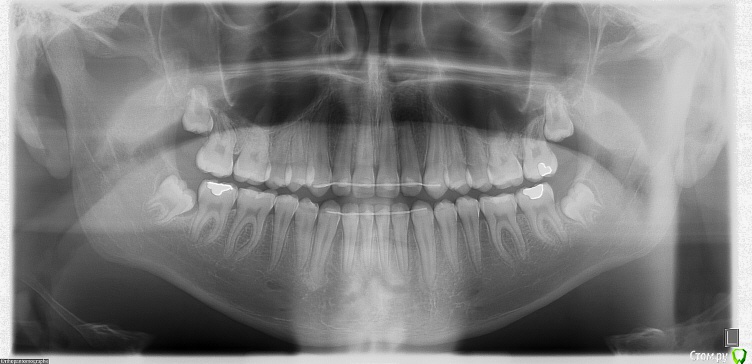

LeoRuss Опубликовано 7 января, 2016 Поделиться Опубликовано 7 января, 2016 Пациенту 17, три месяца назад сняли брекеты которые носили чуть больше года, поставили ретейнеры.Текущий контрольный осмотр у ортодантиста занял пять минут, но..на основе панорамника предписано удалять все восьмерки.Внимательно просмотрев множество уже существующих здесь постов на сюжет удаления ретинированных и дистопированных зубов мудрости, осознал почему их лучше стоит удалить (особенно лежачую 48ку), увидел почему это лучше сделать раньше, пока не отросли закривульные корни, и не дожидаться «а вдруг», но решился все же создать новую тему и задать свой насущный вопрос:А можно ли не ждать, но попытаться их как то сохранить, а еще лучше и поправить расположение этих, еще не выпуклившихся, но уже сформировавшихся рудиментов??Наверняка же были уже пациенты, врачи, времена когда этот вопрос всесторонне отпрепарировали? Пошлите меня пожалста куданить где можно получить данную информацию, желательно позитивную. И конечно буду признателен за ваши личные ПМСМ по конкретной ситуации, снимки прилагаю. Ссылка на комментарий

Doc Опубликовано 7 января, 2016 Поделиться Опубликовано 7 января, 2016 Пациенту 17, три месяца назад сняли брекеты которые носили чуть больше года, поставили ретейнеры.Текущий контрольный осмотр у ортодантиста занял пять минут, но..на основе панорамника предписано удалять все восьмерки.Внимательно просмотрев множество уже существующих здесь постов на сюжет удаления ретинированных и дистопированных зубов мудрости, осознал почему их лучше стоит удалить (особенно лежачую 48ку), увидел почему это лучше сделать раньше, пока не отросли закривульные корни, и не дожидаться «а вдруг», но решился все же создать новую тему и задать свой насущный вопрос:А можно ли не ждать, но попытаться их как то сохранить, а еще лучше и поправить расположение этих, еще не выпуклившихся, но уже сформировавшихся рудиментов??Наверняка же были уже пациенты, врачи, времена когда этот вопрос всесторонне отпрепарировали? Пошлите меня пожалста куданить где можно получить данную информацию, желательно позитивную. И конечно буду признателен за ваши личные ПМСМ по конкретной ситуации, снимки прилагаю. V Panoramique_05-01-2016.JPGV Profil_05-01-2016.JPGТак сохранить-то как раз не проблема. В Вашем случае даже есть шанс, что они вырастут и встанут на место, но при этом они так подвинут весь зубной ряд, что вся красота может скучиться и все, за что боролись не один год, пойдет прахом. Оно Вам надо? Ссылка на комментарий

колесников Опубликовано 7 января, 2016 Поделиться Опубликовано 7 января, 2016 Вовсе они не лежащие. Удалятся легко. Сейчас самое время. Ссылка на комментарий

diesel87 Опубликовано 7 января, 2016 Поделиться Опубликовано 7 января, 2016 Верхняя левая точно уже никуда сама не выйдет, нижние скорее всего упрутся в семерки и как верно сказал doc, нарушат всю красоту. Ссылка на комментарий

LeoRuss Опубликовано 10 января, 2016 Автор Поделиться Опубликовано 10 января, 2016 Так сохранить-то как раз не проблема. В Вашем случае даже есть шанс, что они вырастут и встанут на место, но при этом они так подвинут весь зубной ряд, что вся красота может скучиться и все, за что боролись не один год, пойдет прахом. Оно Вам надо?У меня опасение в данном случае обратное: есть предпосылки как со стороны моей мамы, у которой после удаления восьмерок зубной ряд довольно быстро разъехался, появились заметные прогалы между оставшимися молярами, все стало там застревать, так и, увы, со стороны жены, у нее зубы не особо плотно набиты, при этом восьмерки на месте, а прикус у сына практически её. Может не удалять их все таки пока, тем более как написал уважаемый diesel87 большая вероятность что верхние так и останутся полностью ретинированными, раз уж они тихо там сидят и не беспокоят? Ссылка на комментарий